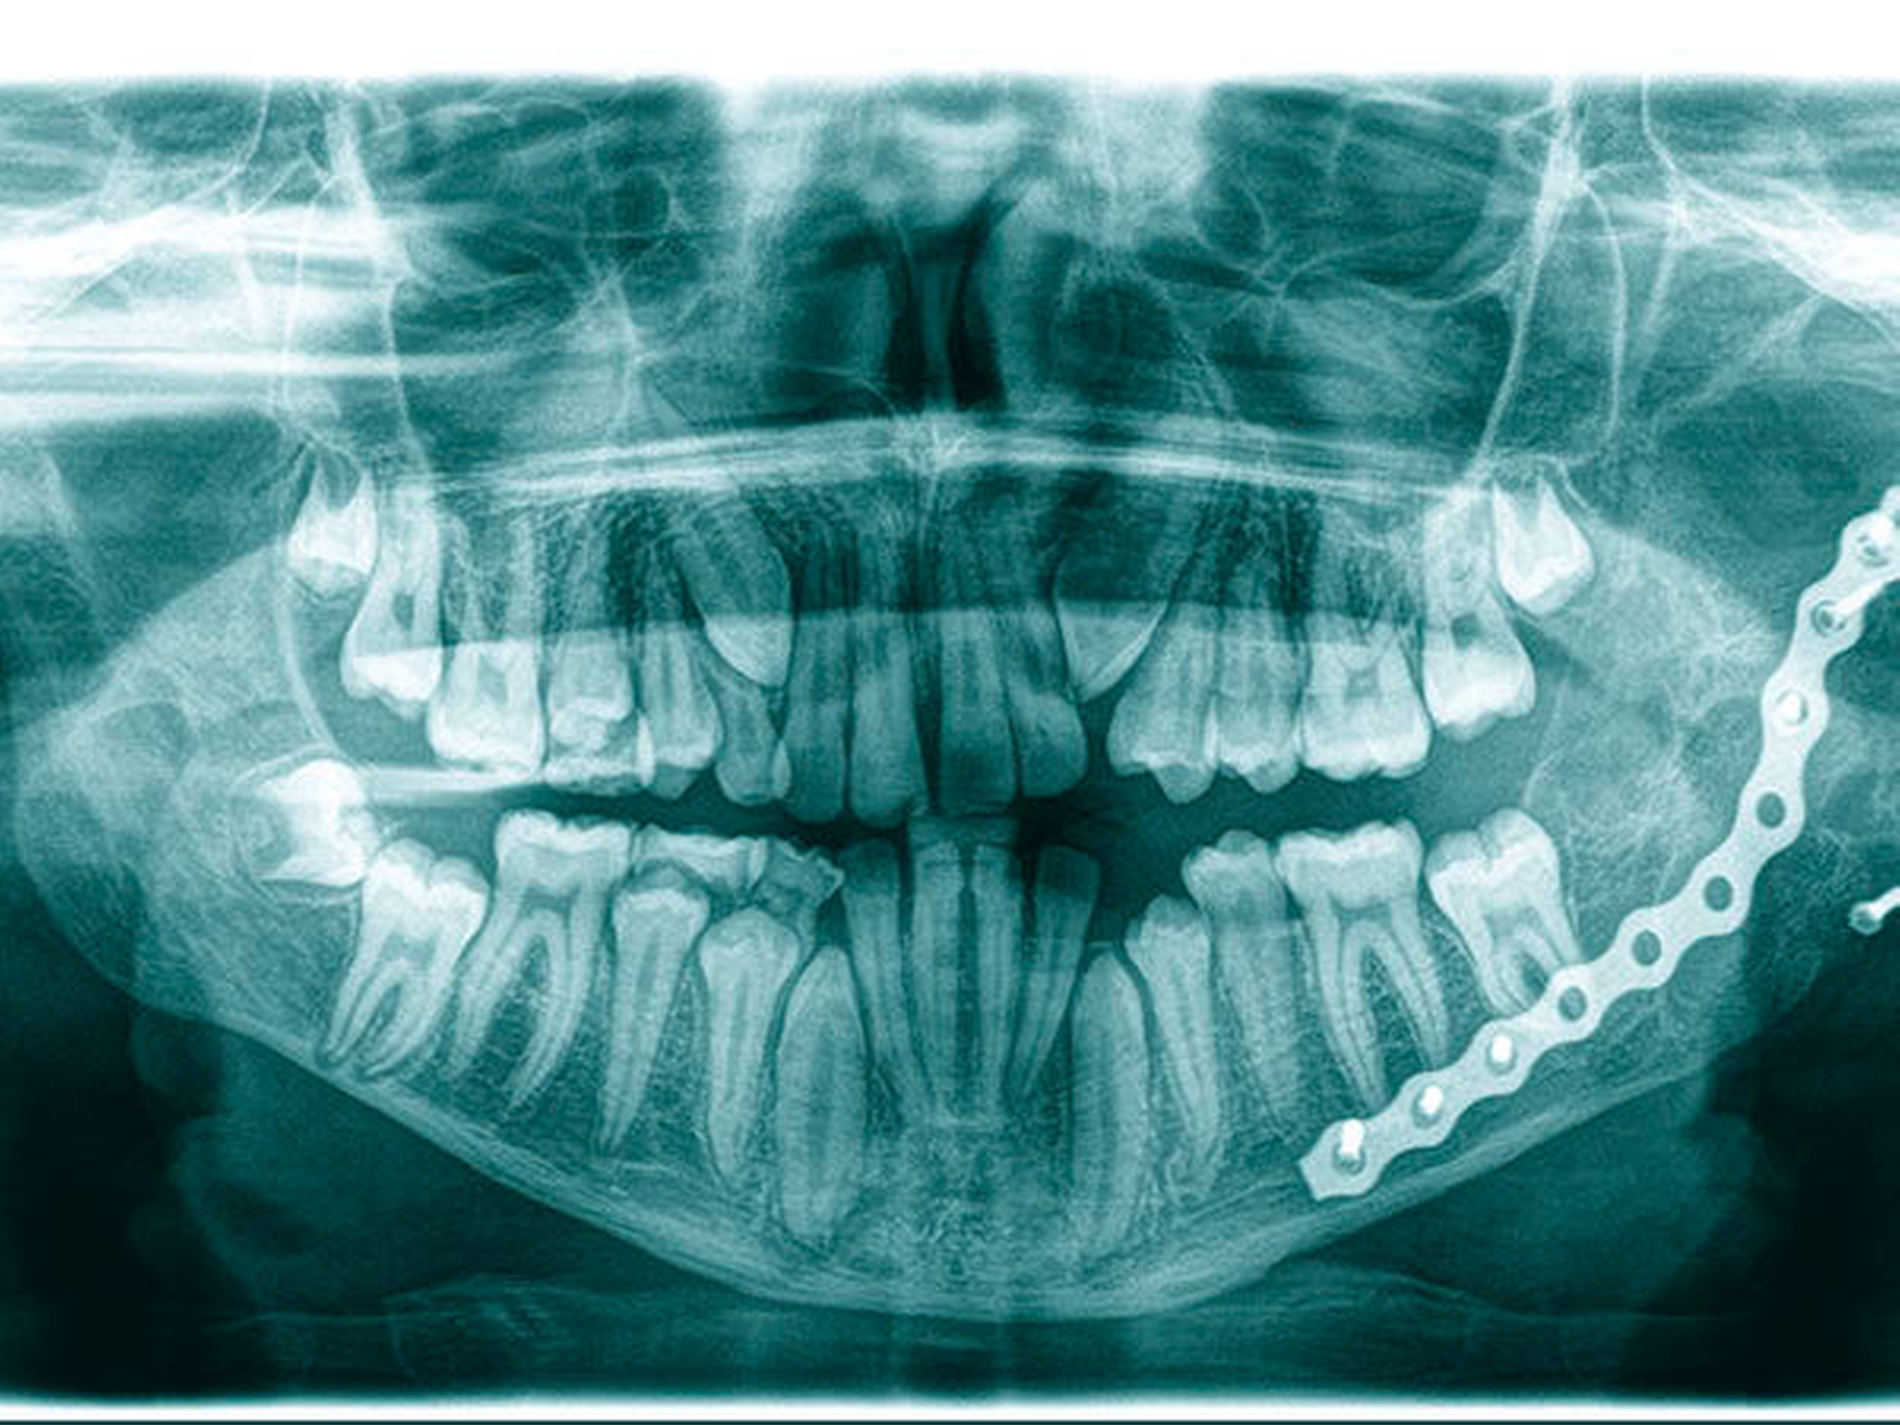

Bei bekannter histologischer Entität wurde ein einzeitiges operatives Vorgehen mit zeitgleicher Exkochleation der Raumforderung im linken Kieferwinkel sowie einer Augmentation durch ein autologes kortikospongiöses Beckenkammtransplantat festgelegt und komplikationslos durchgeführt.

Das histopathologische Bild passte jedoch nach definitiver Aufarbeitung nicht mehr zu dem vordiagnostizierten ossifizierenden Fibrom, sondern vielmehr zu einem zentralen Riesenzellgranulom. Die vorangegangene Histologie konnte jedoch nicht mehr zum Vergleich herangezogen werden. Aufgrund der Diskrepanz wurden die Proben zum DÖSAK-Referenzregister am Institut für Patho‧logie des Universitätsspitals Basel geschickt und der Parathormonspiegel des Patienten zum Ausschluss eines braunen Tumors bestimmt.